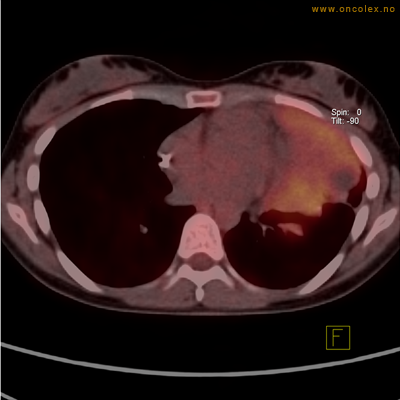

Vev som tar opp mer radioaktivt stoff, synes som hvite områder som lyser opp mer i forhold til annet vev som tar opp mindre sukker.

Moderat opptak i bløtvevssarkom venstre halvdel av brystkassen. Områder med lavere opptak antas å skyldes dels betennelse som skyldes svulsten, dels svulstnekrose.

Moderat opptak av FDG i bløtvevssarkom venstre halvdel av brystkassen. Områder med lavere opptak antas å skyldes dels betennelse som skyldes svulst, dels svulstnekrose.